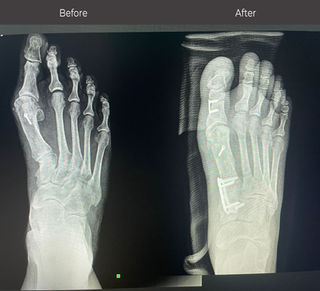

Bunion Surgery

Before and After Photos